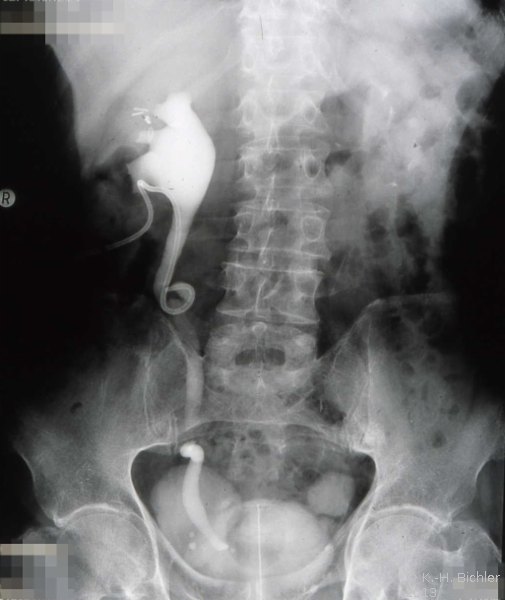

Als Komplikation ausgedehnter Mündungsdivertikel kommt es zu Abflussbehinderungen mit entsprechender Beeinträchtigung der Nierenfunktion. Als Beispiel die Harnstauungsniere bei einem Erwachsenen mit Abflussbehinderung durch ein ausgedehntes Mündungsdivertikel. Zunächst Harnableitung, dann Divertikelabtragung und Reimplantation (Abbildung HG1).